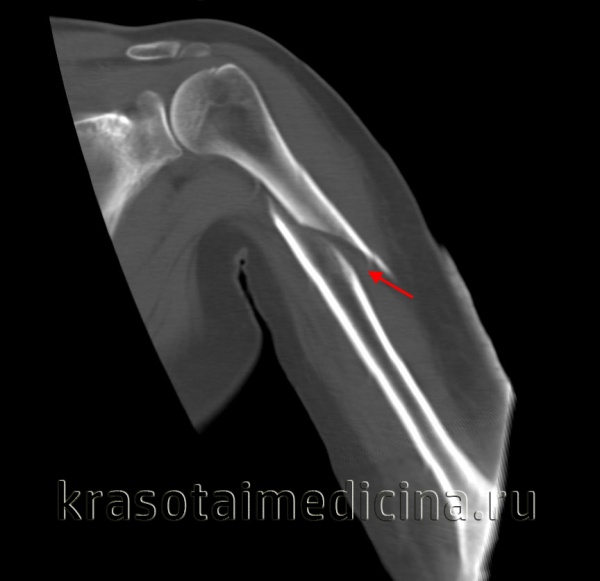

(Слева) На передне-задней рентгенограмме определяется перелом хирургической шейки плеча и переломы, включающие большой бугорок и малый бугорок. Переломы бугорков изолируют суставной отломок, что приводит к повышению риска а васкулярного некроза.

(Справа) На осевой КТ у этого же пациента визуализируются смещенные костные отломки в результате перелома головки плечевой кости и малого и большого бугорка. Поскольку произошло как смещение >1 см, так и отклонение >45° при всех трех видах переломов, это перелом из четырех сегментов.